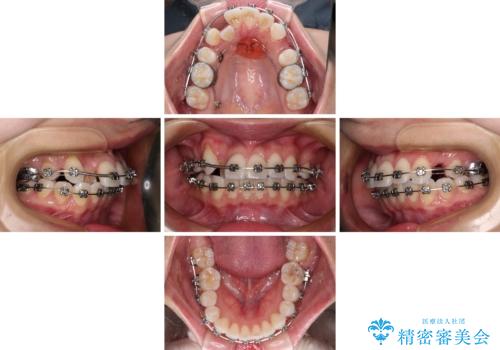

- メタルブラケット

- 2年10ヶ月

- 30回以上

奥歯の咬み合わせを維持しながら正中位置を改善するために、補助装置を使用しました。

予定より期間がかかりましたが、上下の正中位置を綺麗に一致させることができました。